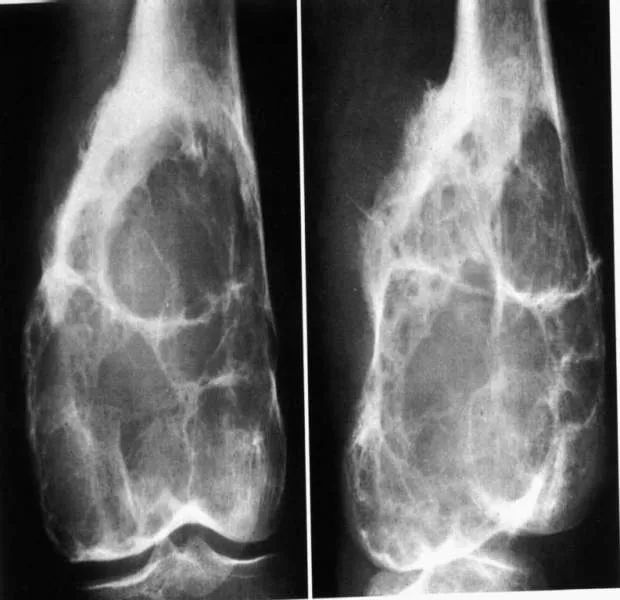

•偏心性:晚期在中央

•膨胀性:膨胀明显时只有薄层骨壳

•分房型:多见,可见数量不等,纤细的骨嵴—皂泡状改变 医学百科网 | YxBaike.Com

•溶骨型:少见,无皂泡状骨性间隔 医学百科网 | YxBaike.Com

破坏区内无钙化、骨化 医学百科网 | YxBaike.Com

破坏边缘清楚但不锐利,无硬化边,无骨膜反应 医学百科网 | YxBaike.Com

皂泡状改变 医学百科网 | YxBaike.Com

骨端偏心性溶骨破坏 医学百科网 | YxBaike.Com